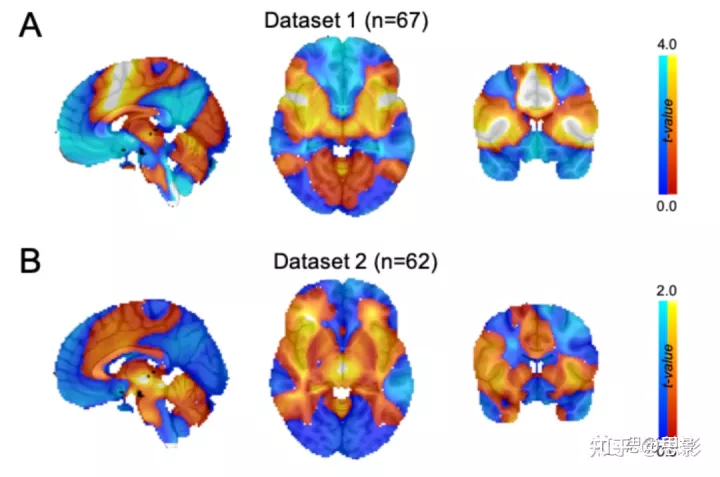

图 S3:当在每个数据集中独立计算时,成瘾缓解网络图是可重现的。

爱荷华州数据集(A)的成瘾缓解网络图类似于罗切斯特数据集(B)的成瘾缓解网络图。 两个网络图之间的空间相关性(r = 0.58)高于预期(置换检验,单边 p = 0.03)。